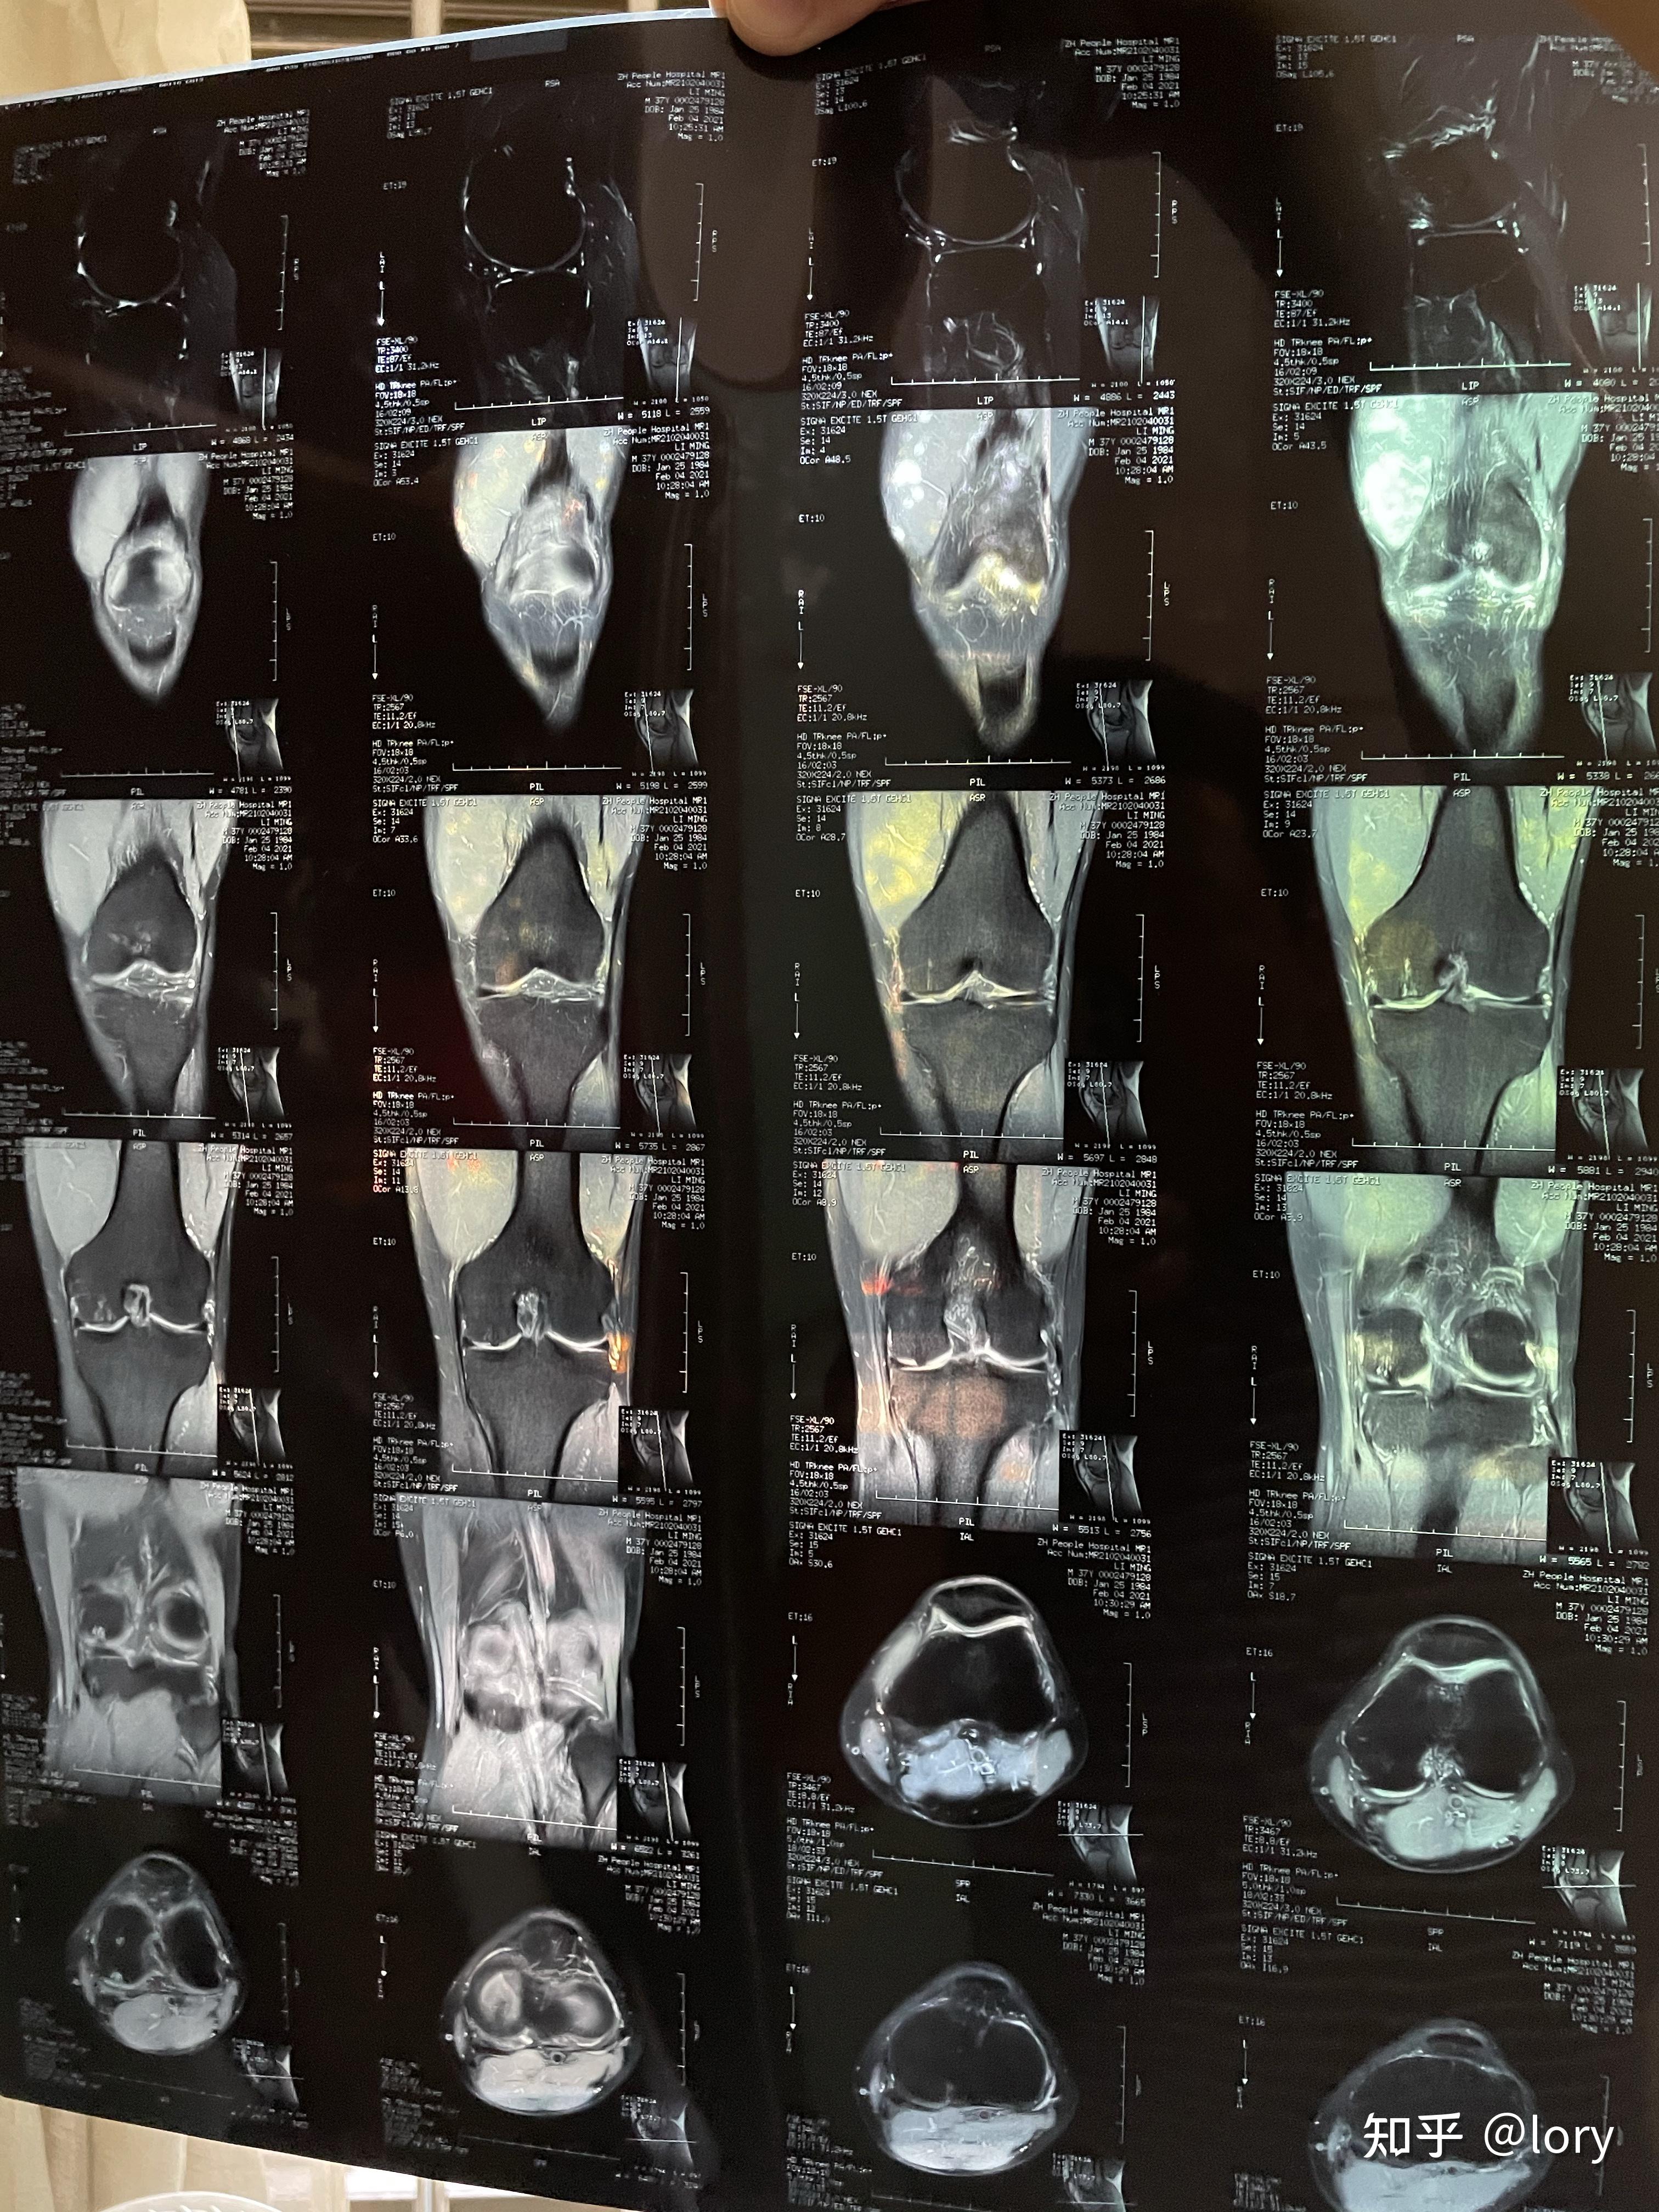

膝盖及腰椎伤病核磁共振结论篮球运动

膝盖及腰椎伤病核磁共振结论篮球运动

求问会看膝盖核磁共振的大神指点一下

膝盖及腰椎伤病核磁共振结论篮球运动